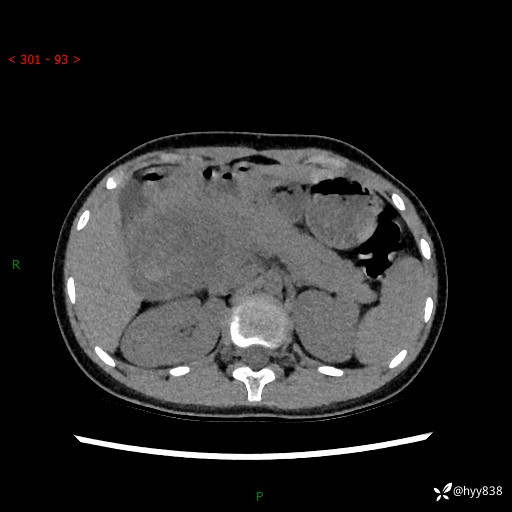

病例小姑娘,超声提示上腹部巨大包块。平扫就能轻松搞定的病变--结果公布

性别:女

年龄:13岁

简要病史:超声提示上腹部巨大包块

上腹部CT平扫

胰腺实性假乳头状瘤 (17)